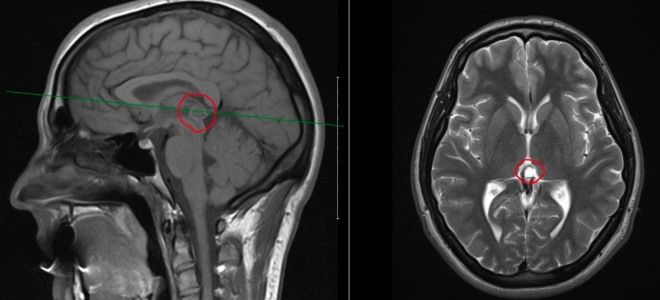

Крупные кистозные образования с необычной формой трудно отличить от опухолей, поэтому пациенты с такими проявлениями должны находиться под постоянным наблюдением. При диагностике врач всегда учитывает магнитно-резонансные признаки мелкой кисты шишковидной железы, которые служат подтверждением.

На экране МРТ данное образование выглядит как однокамерная структура с жидкостным содержимым, обладающая плотностью, аналогичной ликвору, или с такой же интенсивностью сигнала, как спинномозговая жидкость. Для большинства кист характерно наличие кальцинатов – солей, которые образуют ободок вокруг образования (это наблюдается в 25% случаев).